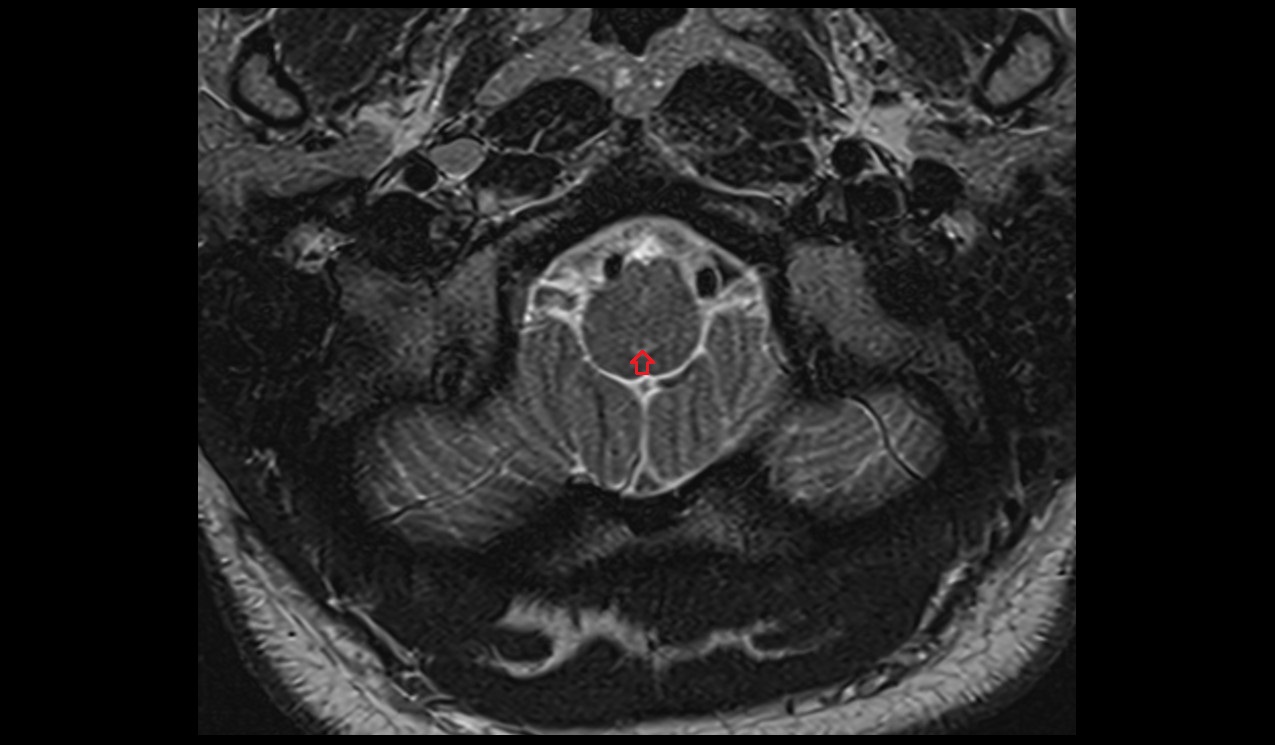

- Upper cervical spinal cord

- Spinal cord